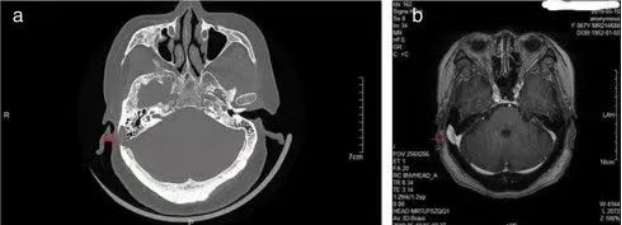

1. 颞骨CT(图5a):快速定位乙状窦憩室的位置、大小,查看是否压迫周围结构,是初步筛查的“首选”;

2. MRI/增强MRI(图5b):更清晰地显示憩室的血流情况,排除其他血管问题(如动静脉瘘),为治疗方案提供依据。

a、b(红色箭头所指为乙状窦憩室)